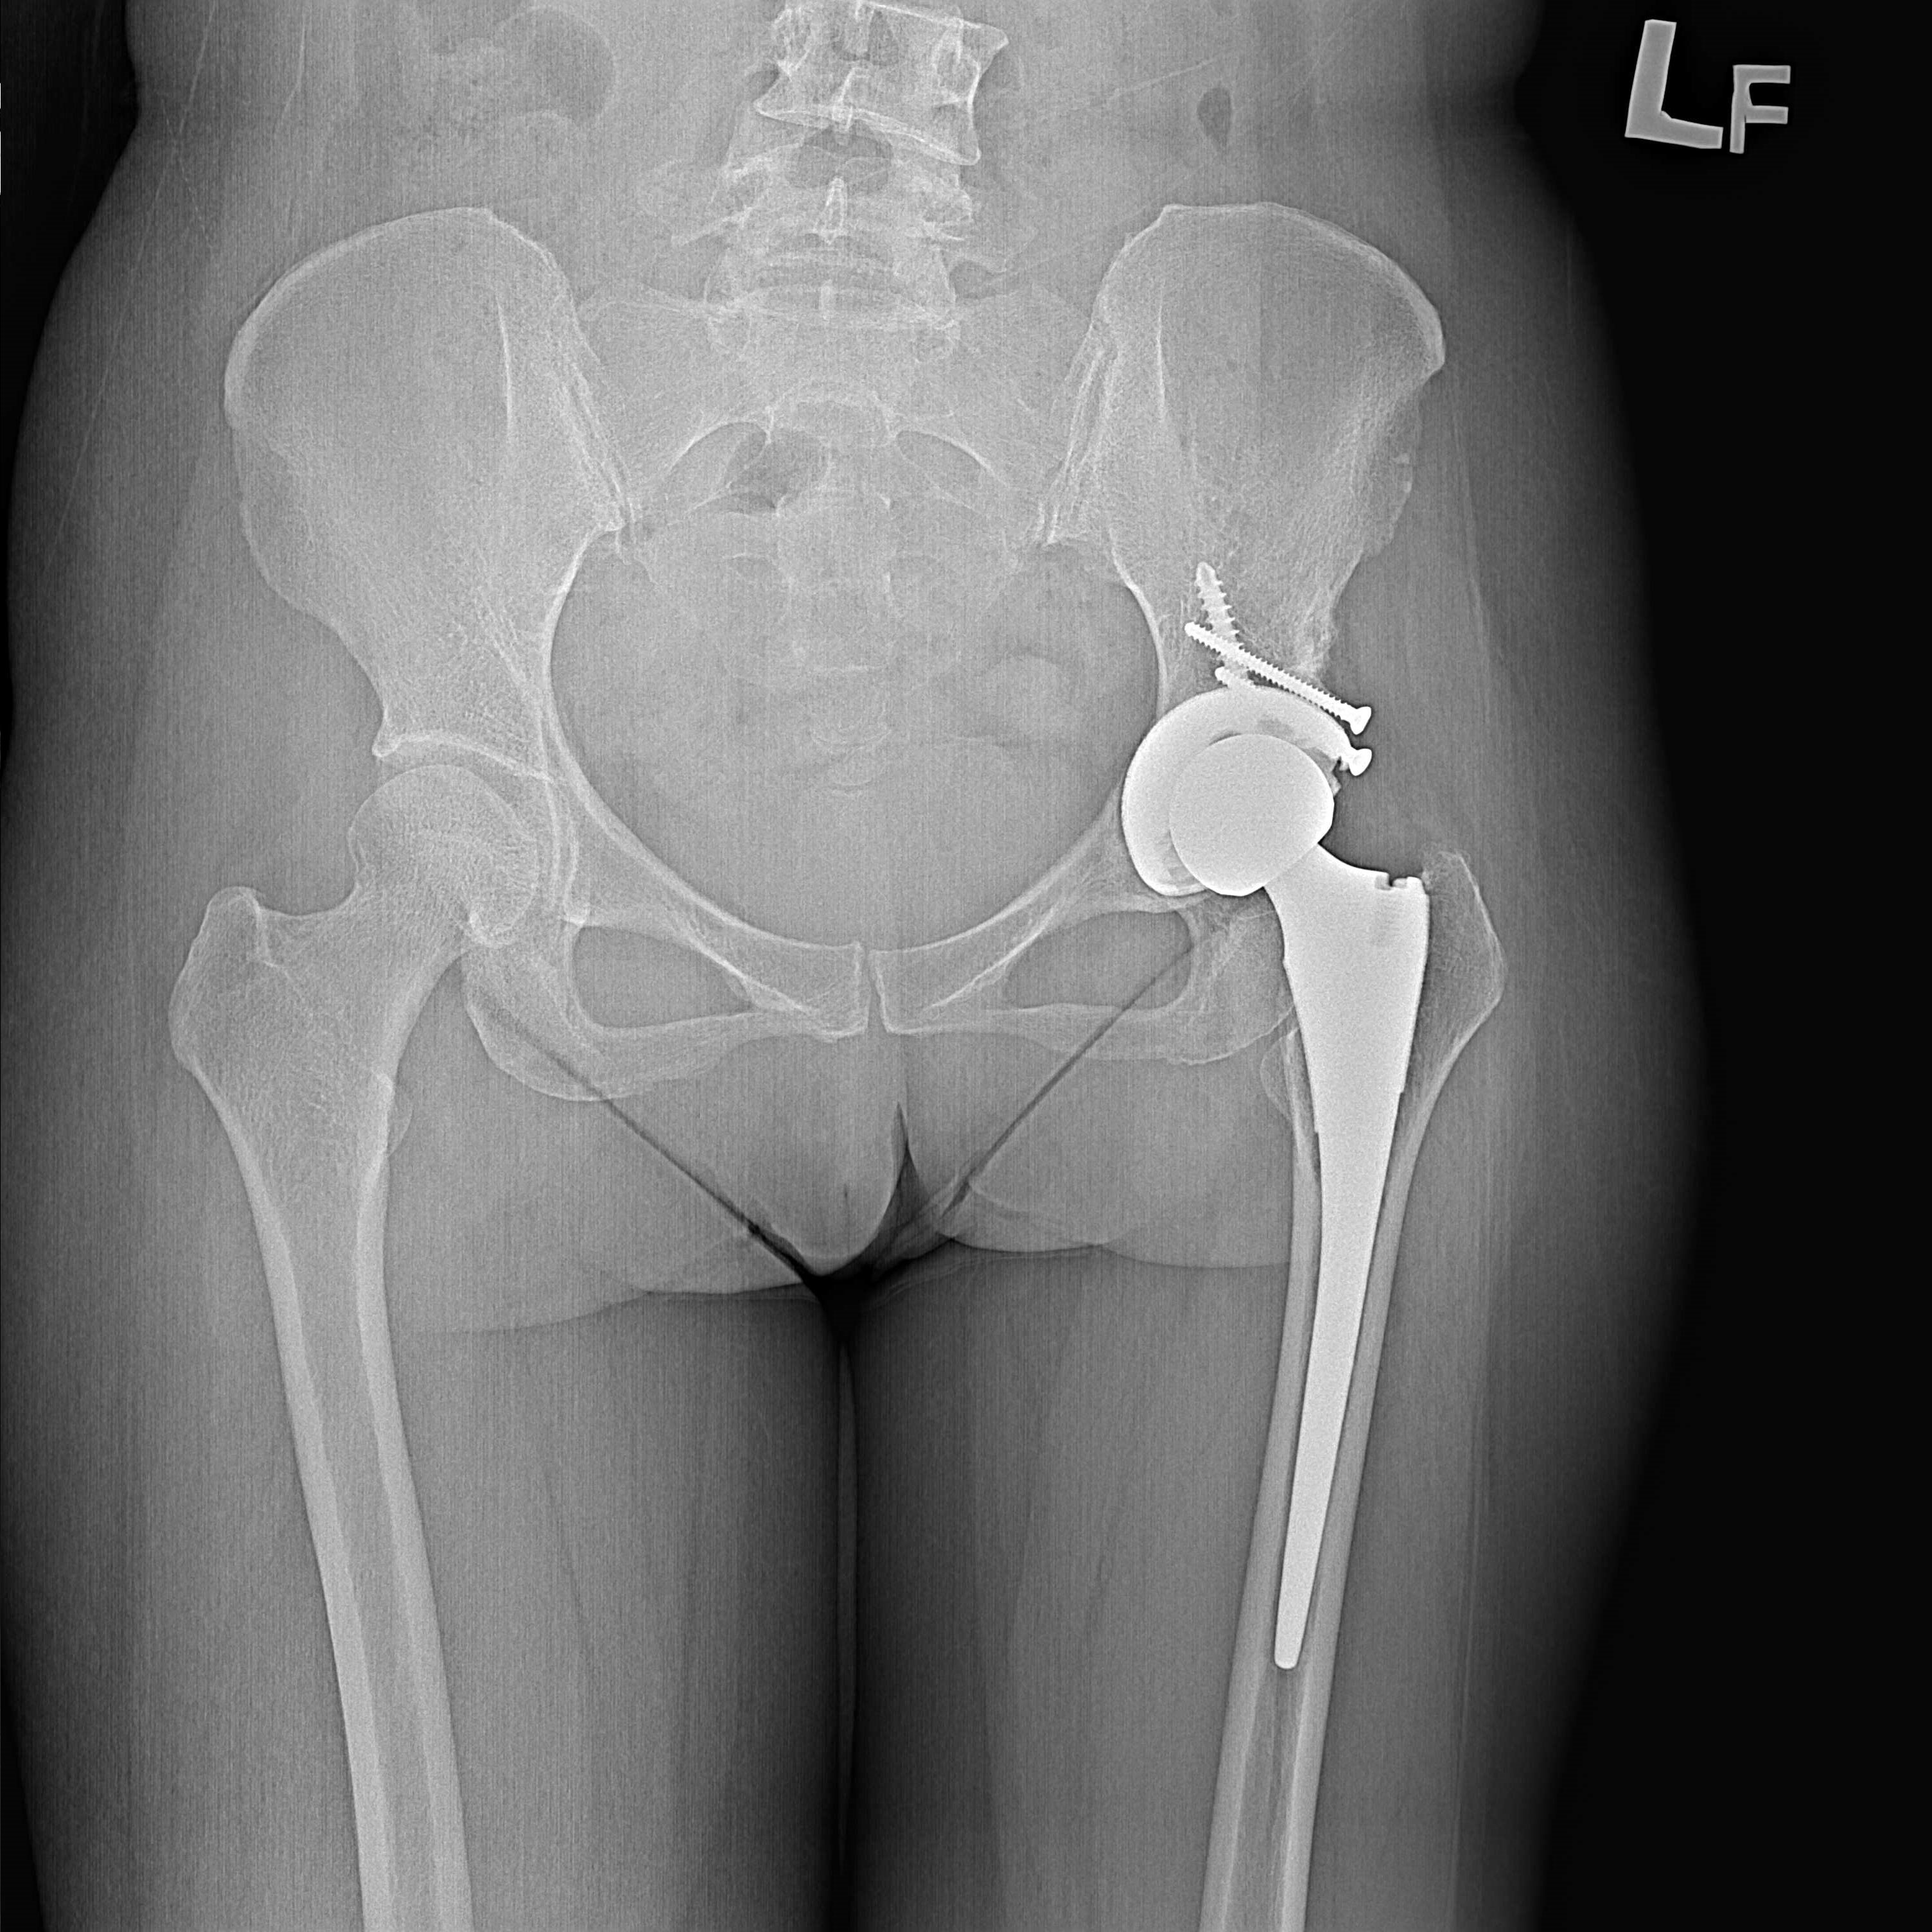

傳統髖關節置換 首頁 案例分享 髖關節手術 傳統髖關節置換 54歲蔡先生退化性關節炎 術前 術後 張女士 51歲 退化性關節炎(DDH先天發育不全 CROWE TYPE 2) 術前 術後 38歲林先生 退化性關節炎 術前 術後 72歲謝女士 退化性關節炎 術前 術後 71歲 謬女士 骨股頭壞死 術前 術後 50歲 郭先生骨股頭壞死 術前 術後 80歲 盧先生骨股頭壞死 術前 術後 林先生 37歲 術前 術後 邱女士 51歲 術前 術後 張女士 50歲 術前 術後